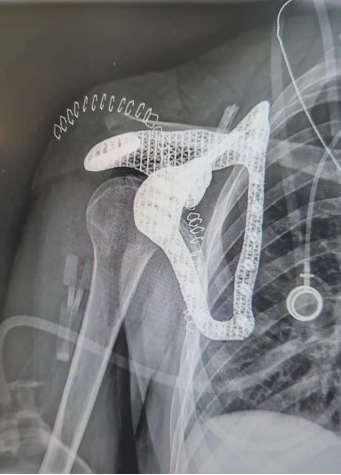

在特拉維夫醫(yī)療中心,一位年輕的患者被診斷出患有罕見的癌癥,數(shù)月來一直飽受疼痛和活動受限的困擾:核磁共振成像顯示,肩胛骨(肩胛骨)廣泛受損,侵襲性腫瘤浸潤周圍肌肉。前方是一條充滿挑戰(zhàn)的道路,當(dāng)務(wù)之急是切除受影響的骨骼,同時盡可能保留肩部功能。 患者最初接受了化療以縮小腫瘤,但仍有必要進行肩胛骨全切除術(shù)。面對可能使患者失去肩部功能的手術(shù),特拉維夫醫(yī)療中心專家與PTC和Hexagon的團隊選擇了另一條道路:他們將設(shè)計并植入一個定制的3D打印鈦合金肩胛骨,并根據(jù)患者的獨特解剖結(jié)構(gòu)進行制作。這種方法不僅能恢復(fù)患者的活動能力,還有助于重新定義未來復(fù)雜骨骼手術(shù)的治療方案。

顯然,PTC和Hexagon的團隊此刻需要找到一種方法,為這名年輕的癌癥患者定制肩胛骨植入物。而該項目需要極高的精度來解決復(fù)雜的問題,團隊需要找出一種方法,在解剖、醫(yī)療、工程、制造和認(rèn)證限制之間實現(xiàn)理想的平衡。 在特拉維夫醫(yī)療中心專家的指導(dǎo)下,PTC和Hexagon團隊利用Creo快速成型制造和高保真模擬設(shè)計工具的強大功能,成功制作出完全個性化的肩胛骨植入物,并利用Hexagon的技術(shù)成功制造和認(rèn)證了該植入物。 手術(shù)按計劃進行,個性化植入體與患者的解剖結(jié)構(gòu)完美契合。通過Creo設(shè)計和Hexagon認(rèn)證工具實現(xiàn)的精確定制部件在患者的快速康復(fù)中發(fā)揮了關(guān)鍵作用,使她能夠在幾天內(nèi)開始恢復(fù)活動能力,這也是植入物所蘊含的卓越工程技術(shù)的最好證明。如今,患者正在進行康復(fù)治療,功能得到了恢復(fù),生活質(zhì)量也得到了提高。